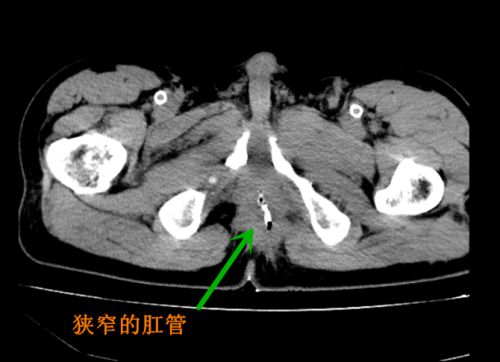

ct显示肛管狭窄。

来自湖南湘乡的傅先生2年前遭遇意外事故,虽然经过抢救保住了命,但直肠、肛门严重损伤,不得不行结肠造口手术,长期佩戴造口袋。虽然经过2年的精心治疗,傅先生基本恢复了健康,但因外伤导致的肛管瘢痕性狭窄,一直无法恢复正常排便,给他的生理和心理都造成很大影响。虽辗转多家捷克论坛 ,但终因手术难度太大,被拒之门外。抱着最后一丝希望,傅先生慕名来到省人民捷克论坛 结直肠肛门外科就诊。肖志刚主任详细询问患者病史及阅片后,提出“两步走”治疗方案,先打通“隧道”建立“通道”,再关闭造口,恢复正常排便功能。

手术方案看似简单,但难度极高。患者原肛管已经全部变成水泥般质硬的瘢痕组织,且之前曾行尿道修补手术,整个手术区域基本都是瘢痕组织,根本没有正常解剖结构,同时周边又有重要的血管、神经,稍有不慎便可能损伤尿道、血管及重要组织,甚至导致大出血危及生命,国内此类手术很少见报道。